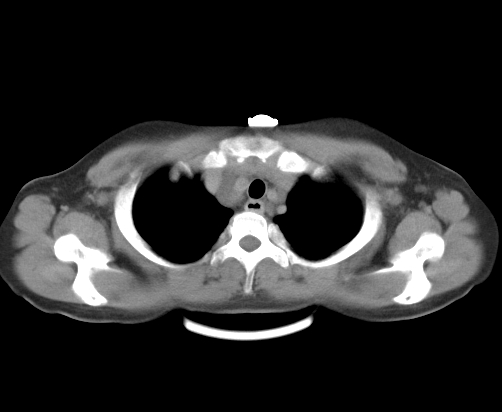

标题: CT23915:女 20岁 全身长疙瘩三年 今日多体位查 看看吧 [打印本页]

标题: CT23915:女 20岁 全身长疙瘩三年 今日多体位查 看看吧

胸部

神经纤维瘤病

支持神经纤维瘤。

支持 神经纤维瘤病。